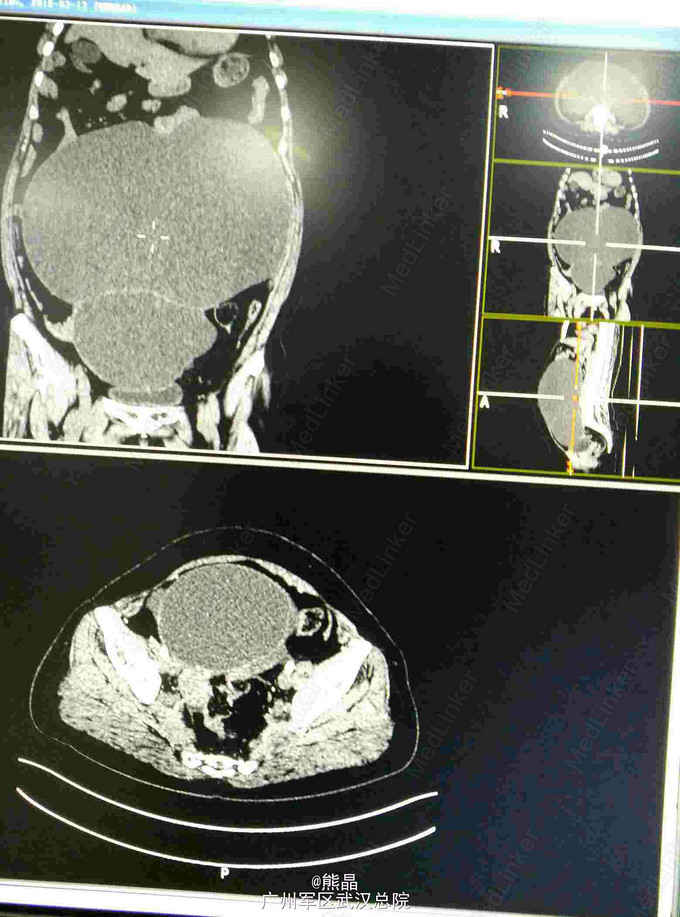

患者女性,58岁,起病缓,病程长,发现腹部膨隆3年余

外阴已婚已产式,阴道通畅,宫颈糜烂,子宫后位,盆腔触及巨大包块,上至剑突,下至耻骨联合。超声:盆腔异常回声,考虑囊腺瘤可能,MRI盆腔巨大良性囊性占位,考虑囊腺瘤可能

手术,病理结果示右侧附件粘液性囊腺瘤